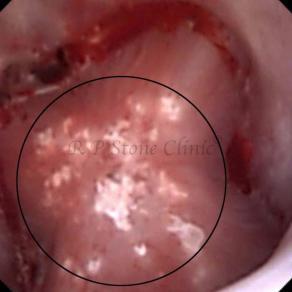

These images are taken as snap shots from the video recording of RIRS Surgery done at our hospital. These are Randall’s Plaques seen with Digital FLEX XC & Digital FLEX XC S. The cream or whitish patches are seen on the tips of RENAL PAPILLAE as seen in images below.

The Below Images Show Small Stones attached to the Renal Papillae.